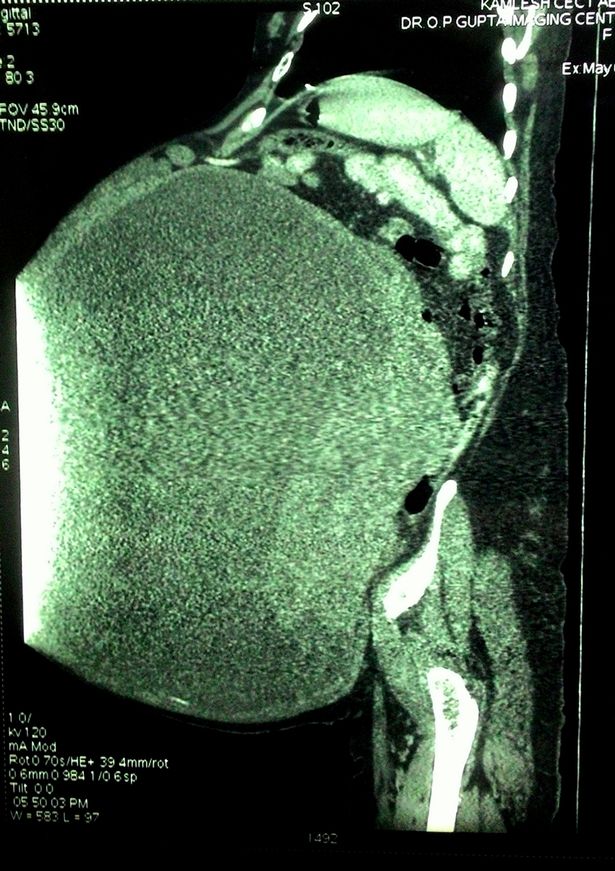

L’operazione è durata solo 3 ore e ha richiesto 3 sacche di sangue. Il tumore era cresciuto così tanto che era arrivato a pesare 97 kg, come se Demi portasse dentro di sé un cucciolo di elefante o 28 neonati di peso medio. “Non ho mai visto una cosa del genere in tutta la vita – ha spiegato il dottor Saggi – Un tumore alle ovaie è comune, ma non di una grandezza simile”. Date le circostanze, l’ospedale ha contattato la versione indiana del libro dei Record per vedere se il tumore di Demi potrà essere considerato un Guinness World Record.